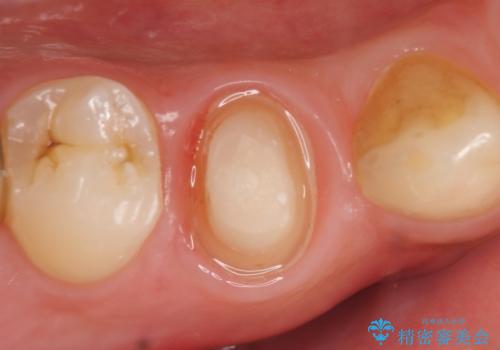

X線上で根尖病変を認めたため再根管治療を行い、症状改善後、オールセラミッククラウンによる補綴を行いました。

- オールセラミッククラウン(st)…¥100,000、仮歯…¥10,000、ファイバーコア…¥20,000費用は治療当時の料金となります

今回用いたオールセラミッククラウンはジルコニアフレームという白い素材の上にセラミックを盛っているため、審美性が非常に高いのが特徴です。

また、ジルコニアは人工ダイヤモンドの材料にも使われているほど高い強度を持っており、そのためオールセラミッククラウンは審美性だけでなく、奥歯やブリッジの補綴も可能とするクラウンです。